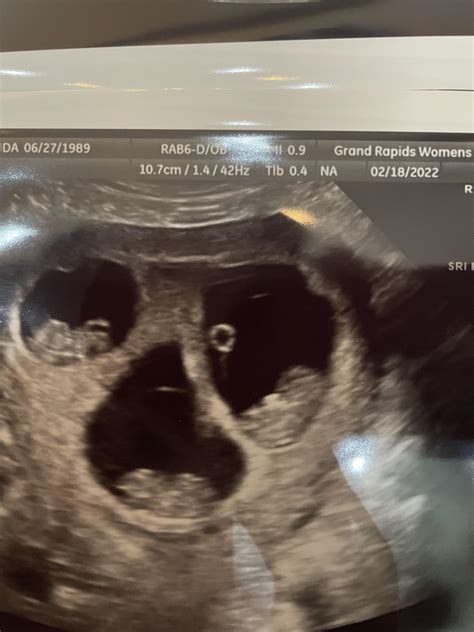

What Can Be Seen During a 9 Weeks Ultrasound?

At 9 weeks, the fetus is still very small, but several key features can be visualized:

• Gestational Sac: This is the fluid-filled structure that contains the embryo.

• Yolk Sac: This structure provides early nutrition to the embryo.

• Embryo: The embryo itself, which is about the size of a grape, can be seen with a distinct head and body.

• Fetal Heartbeat: The heartbeat is usually visible and audible, providing reassurance of the fetus’s health.

• Amniotic Fluid: The fluid surrounding the embryo, which protects and cushions the developing fetus.

📝 Note: The clarity of the images can vary based on factors such as the position of the uterus, the amount of amniotic fluid, and the skill of the technician.